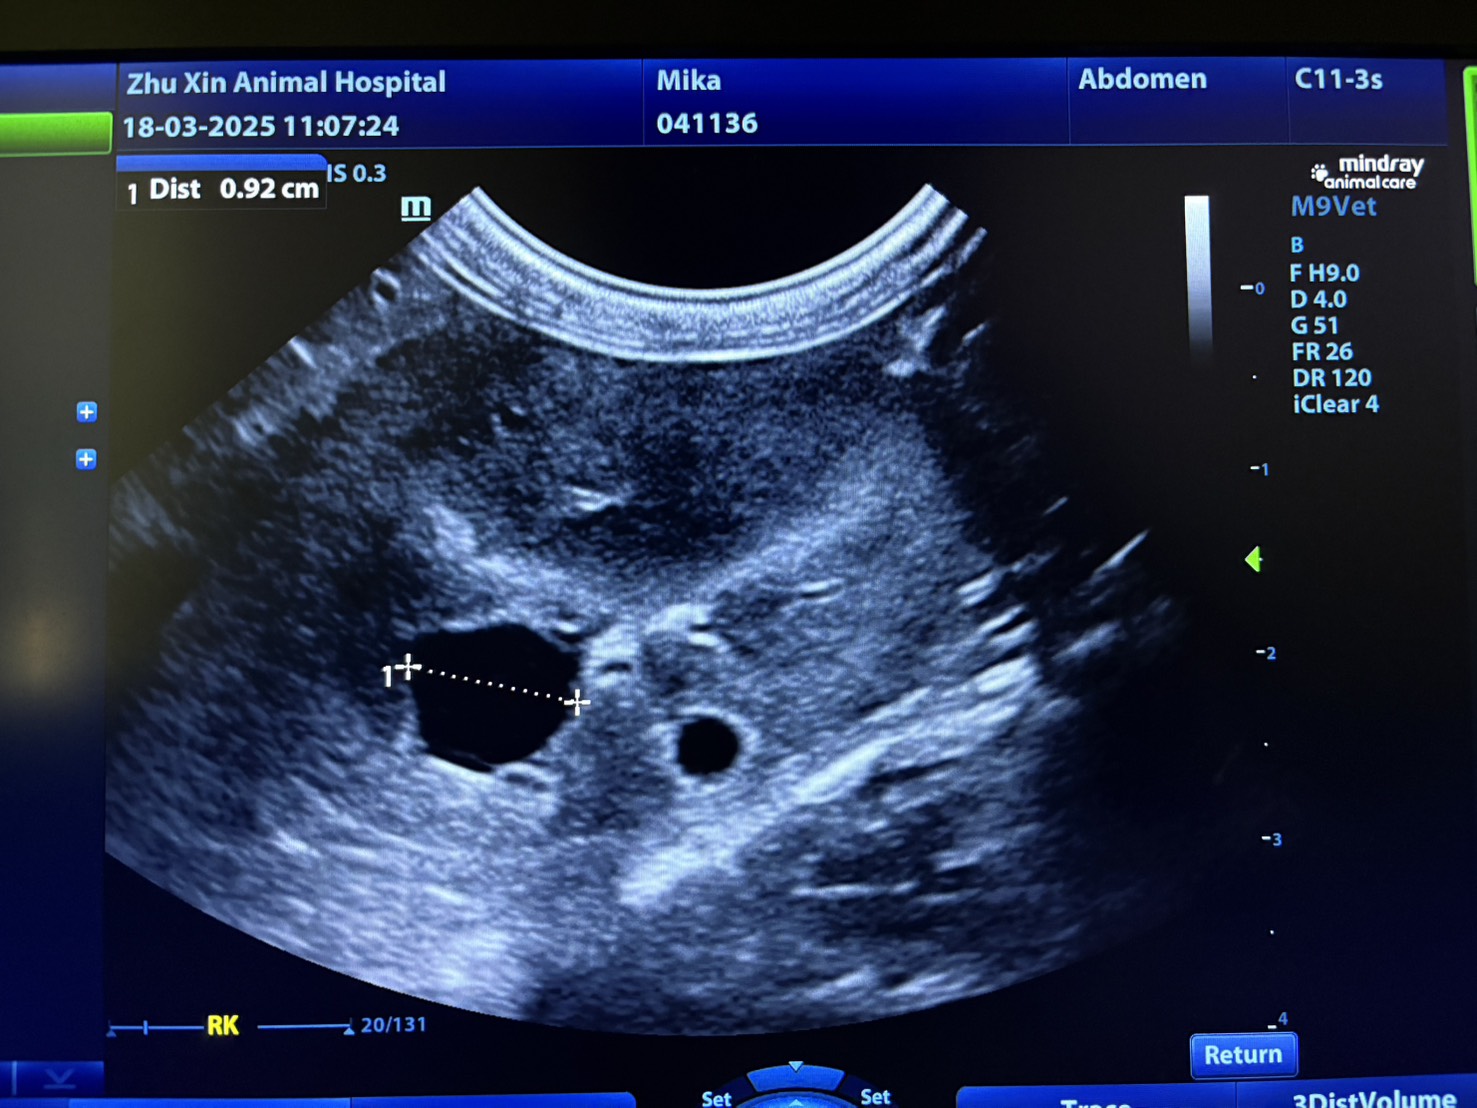

超音波檢查:診斷多囊腎的主要工具,可檢查腎臟結構是否有囊腫。

酒精硬化治療(Ethanol sclerotherapy):在超音波影像導引下,將穿刺針放進囊腫內,將囊腫液抽乾,再使用高濃度的酒精破壞囊腫內的細胞,使其壞死不再產生囊腫液。